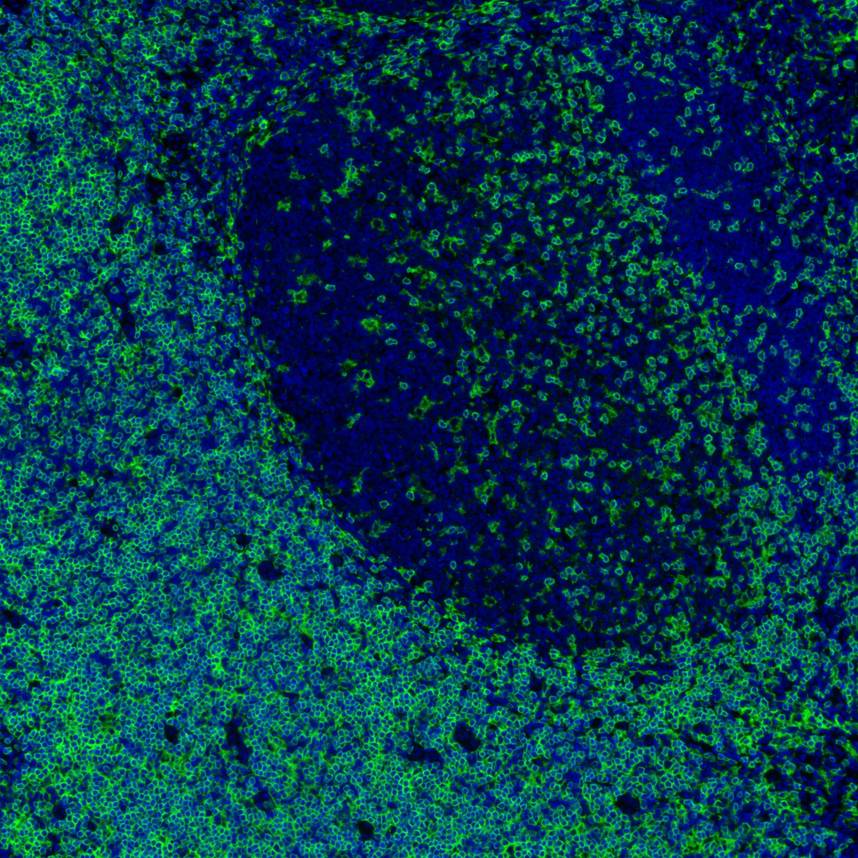

IRS005_4.jpg Fig4: mIHC analysis of human tonsil tissue (Formalin/PFA-fixed paraffin-embedded sections) with Rabbit anti-CD4 antibody (IRS005) at 1/100 dilution. The immunostaining was performed with the IRISKitCmTSA Kit (900808). Heat mediated antigen retrieval with Tris-EDTA buffer (pH 9.0) for 30 mins at 95℃. DAPI (blue) was used as a nuclear counter stain. Image acquisition was performed with Olympus VS200 Slide Scanner.